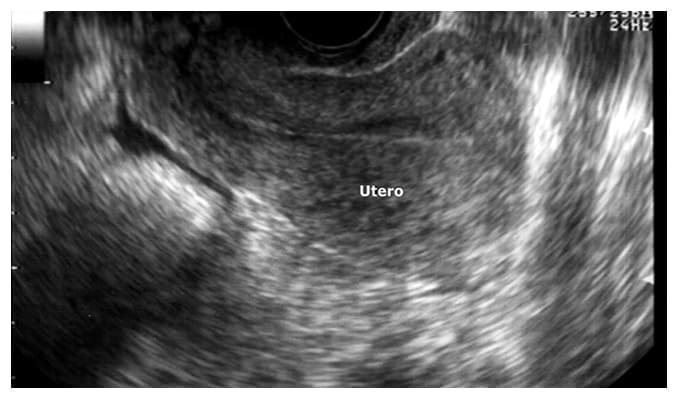

Ultrasonido ginecológico endovaginal.